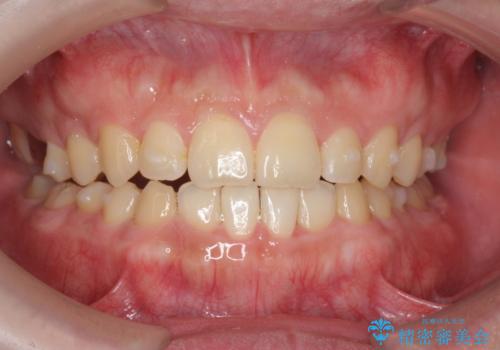

- 前歯の噛み合わせが反対になっていること、前歯の見た目の改善を希望され来院されました。

詳細な矯正検査の結果、顎の歪みが見られたため大きく歯を動かす治療ではなく前歯を主に並べることで前歯の前後関係を改善していきます。

前歯を主に動かす部分矯正であることからマウスピース矯正インビザラインによる治療を計画します。